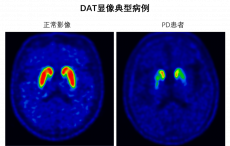

西京医院引入“大脑GPS”:为老年痴呆、帕金森精准诊断开新局

阿尔茨海默病(老年痴呆)与帕金森病,作为两种常见的脑部疾病,犹如隐匿在暗处的“健康杀手”,给患者及其家庭带来沉重负担。这...